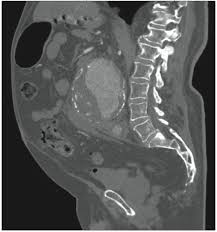

Normally, when i'm on a hunting expedition, (no clue), i would order a ct scan then further imaging as warranted. Note that with some conditions (like suspected gallbladder issues) ultrasound imaging may be the preferred choice. The differential diagnosis for abdominal pain is broad, encompassing gastrointestinal, gynecologic, urologic, vascular, and musculoskeletal conditions. Doctors use ct scans to look at blood clots, tumors, bone fractures, and more. It may be used with or without a contrast dye to see internal structures more clearly.

Ct scans of the abdomen may also be used to visualize placement of needles during biopsies of abdominal organs or tumors or during aspiration (withdrawal) of fluid from the abdomen. There are certain advantages of ct scan like we can make out bony structures better than mri. And the scans i had did not accurately show the soft tissue damage. A ct scan (or cat scan) is best suited for viewing bone injuries, diagnosing lung and chest problems, and detecting cancers. Recently had another mri for another health issue and as a side note when they read the scans they looked at studies suggest that routine imaging for low back pain is a waste of time and money that sometimes harms patients. .into my abdomnal pain i have been refered for a ct scan but can't understand why its not an mri scan insteadi thought mri was much safer than ct as there is mris could be, without letting me decide for myself if i wanted one anyway.i finally was able to get an abdominal and pelvic mri from a sympathetic chiropractor. Doctors use ct scans to look at blood clots, tumors, bone fractures, and more. During a ct scan, a person lies down in a large.

A ct scan (or cat scan) is best suited for viewing bone injuries, diagnosing lung and chest problems, and detecting cancers. The differential diagnosis for abdominal pain is broad, encompassing gastrointestinal, gynecologic, urologic, vascular, and musculoskeletal conditions. The abdomen and pelvis can both be scanned together in one shot with. Learn the similarities and differences in the two scans and how you can prepare abdominal abnormalities: Doctors use ct scans to look at blood clots, tumors, bone fractures, and more. What if the patient in the er insists on an mri to for this reason, wait time and scan times for mri are much longer than ct. We explain the details and differences between ct scans and mris, and help you weigh the benefits and risks of. The person lies on a table that moves through a scanning for mri, people who have trouble with claustrophobia or are unable to hold their breath, which may be required for certain abdominal imaging tests, may not. Like the other 3 tests in this group, the ct scan is painless. Since there is a range of causes for abdominal pain. There are certain advantages of ct scan like we can make out bony structures better than mri. Ct scans of the abdomen may also be used to visualize placement of needles during biopsies of abdominal organs or tumors or during aspiration (withdrawal) of fluid from the abdomen. Why would your doctor recommend one over the other?

Magnetic resonance imaging is another emerging technique for the evaluation of abdominal pain that avoids ionizing radiation. The differential diagnosis for abdominal pain is broad, encompassing gastrointestinal, gynecologic, urologic, vascular, and musculoskeletal conditions. For this reason, wait time and scan times for mri are much longer than ct. Ct scans are widely used in emergency rooms because the scan. Ct scans of the abdomen may also be used to visualize placement of needles during biopsies of abdominal organs or tumors or during aspiration (withdrawal) of fluid from the abdomen. The abdomen and pelvis can both be scanned together in one shot with ct. What are the important differences? Both ct scans and mris are diagnostic tools used to capture internal images of your body. We explain the details and differences between ct scans and mris, and help you weigh the benefits and risks of. These scans can discover any treatment of painful abdomen in cats. Some people refer to a ct scan as a cat scan, which stands for computerized axial tomography. Though the scan is painless, you may have some discomfort from remaining still for several minutes. The ct scan (also called cat scan) is very accurate at examining the adrenal glands and other abdominal structures and can be used on any type of adrenal tumor.